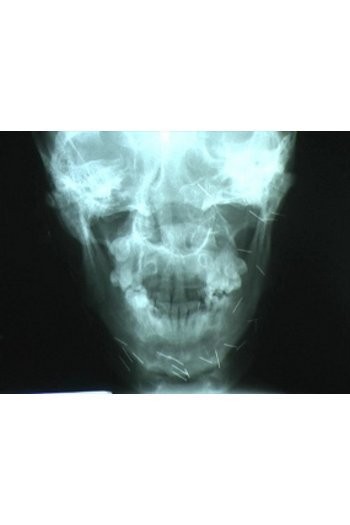

5. Dwi Priyo Santoso (25), puluhan jarum bersarang di kepala

Setelah beberapa kali dibawa ke dukun, akhirnya Dwi berobat ke RS Mardi Waluyo, Blitar. Pihak RS merujuk Dwi agar berobat ke RS Syaiful Anwar, Malang. Namun tim dokter menduga logam mirip jarum yang bersarang di kepala Dwi adalah susuk dan dari situ dokter menduga Dwi menderita tumor hidung.